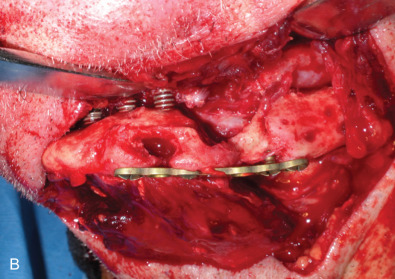

All of these systems allowed for convalescent function – life without MMF. RIF had the potential of dramatically shortening the course of treatment. However, its use was highly technique-sensitive with a steep learning curve. Thus, the incidence of complications increased dramatically due to operator error. Complications related to inadequate reduction – “the OIF” (open internal fixation … without the reduction) ( Figs. 1.16.1–1.16.3 ), inadequate fixation ( Figs. 1.16.4–1.16.7 ) and surgical misadventure ( Fig. 1.16.8 ) began to appear. Indeed, by the early 1990s operator error was the number one cause of mandibular fracture complications. Quite obviously, RIF is very unforgiving. When done poorly, one has a rigidly fixed mistake. The latest series of misadventures are related to the use of IMF screws. Bone-anchored arch bars will most likely be next. Not all believe that RIF and convalescent function is cost-effective with respect to the increased cost, potential for complications, and patient acceptance.